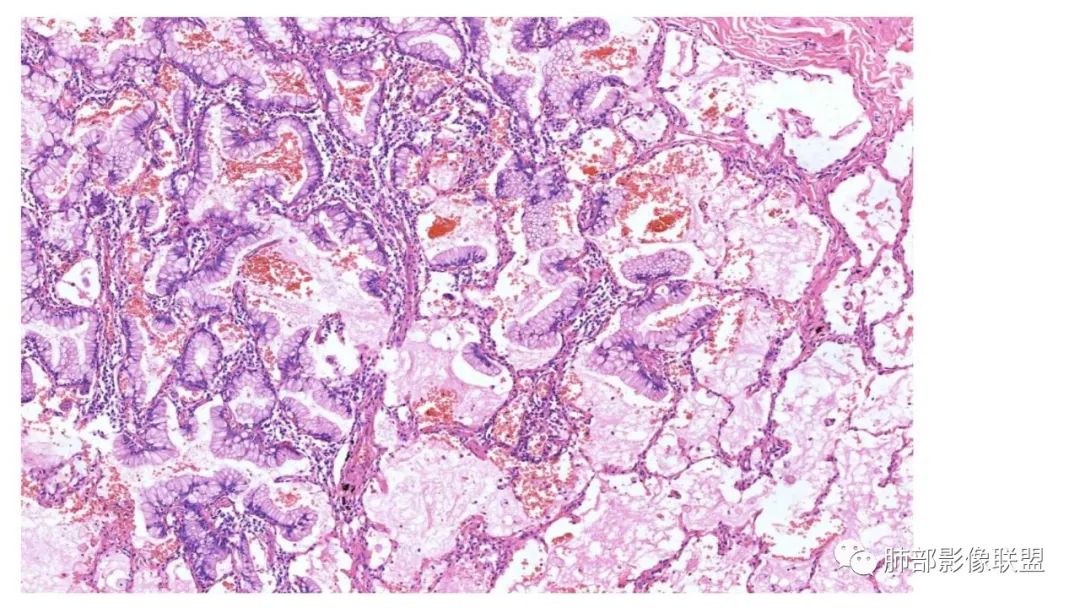

粘液腺癌影像上分为:结节型及斑片型/混合(肺炎型)。

一、结节型粘液腺癌和普通腺癌类似,重视体检及复查不易遗漏

2.病变周围GGO,边界清楚或稍模糊。圆圈征、草帽征、树上蘑菇征等。

3.结节型发展缓慢,淋巴结转移少见。

4.无明显强化或低强化。